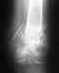

После реостеосинтез с рассверливанием обычно срастается. Про осколок думать не надо, пусть остается, где есть. Должно срастись хотя бы по передней поверхности. С гвоздем внутри запас времени будет очень большой, риск повторного перелома из-за асимметричного сращения отсуствует.

Если не сросся вертельный перелом, это даже хорошо, т.к. можно было бы исправить положение и там. Вы показали только одну проекцию, полноценно оценить сращение не получится.